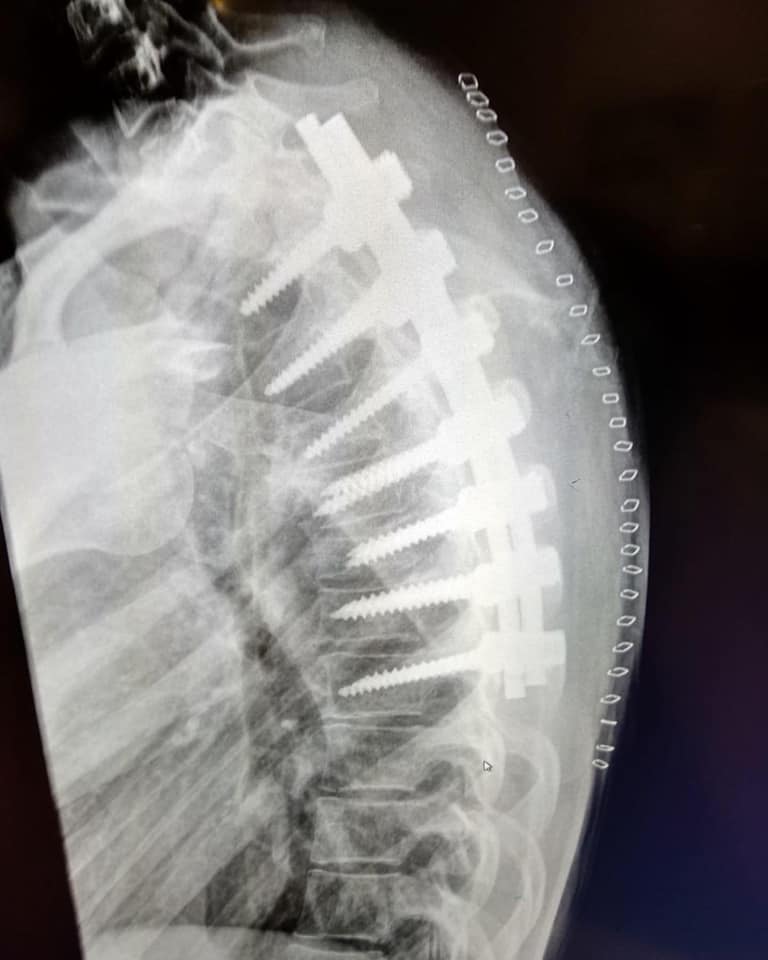

Ana Carrasco在今年1月12日接受最新的手術,用來移除去年意外過後,植入脊椎增加復原速度的,這些植入物是自從去年9/15以來,一直待在Ana Carrasco脊椎周圍的零件,會在今年初就進行移除,則是因為醫師評估Ana Carrasco的復原狀況超乎預期的好,而提前做的措施。目前醫師表示兩週後傷口癒合,Ana Carrasco就可以開始進行運動訓練,再經過兩週估計就可以實際跨上賽車,準備2021賽季!